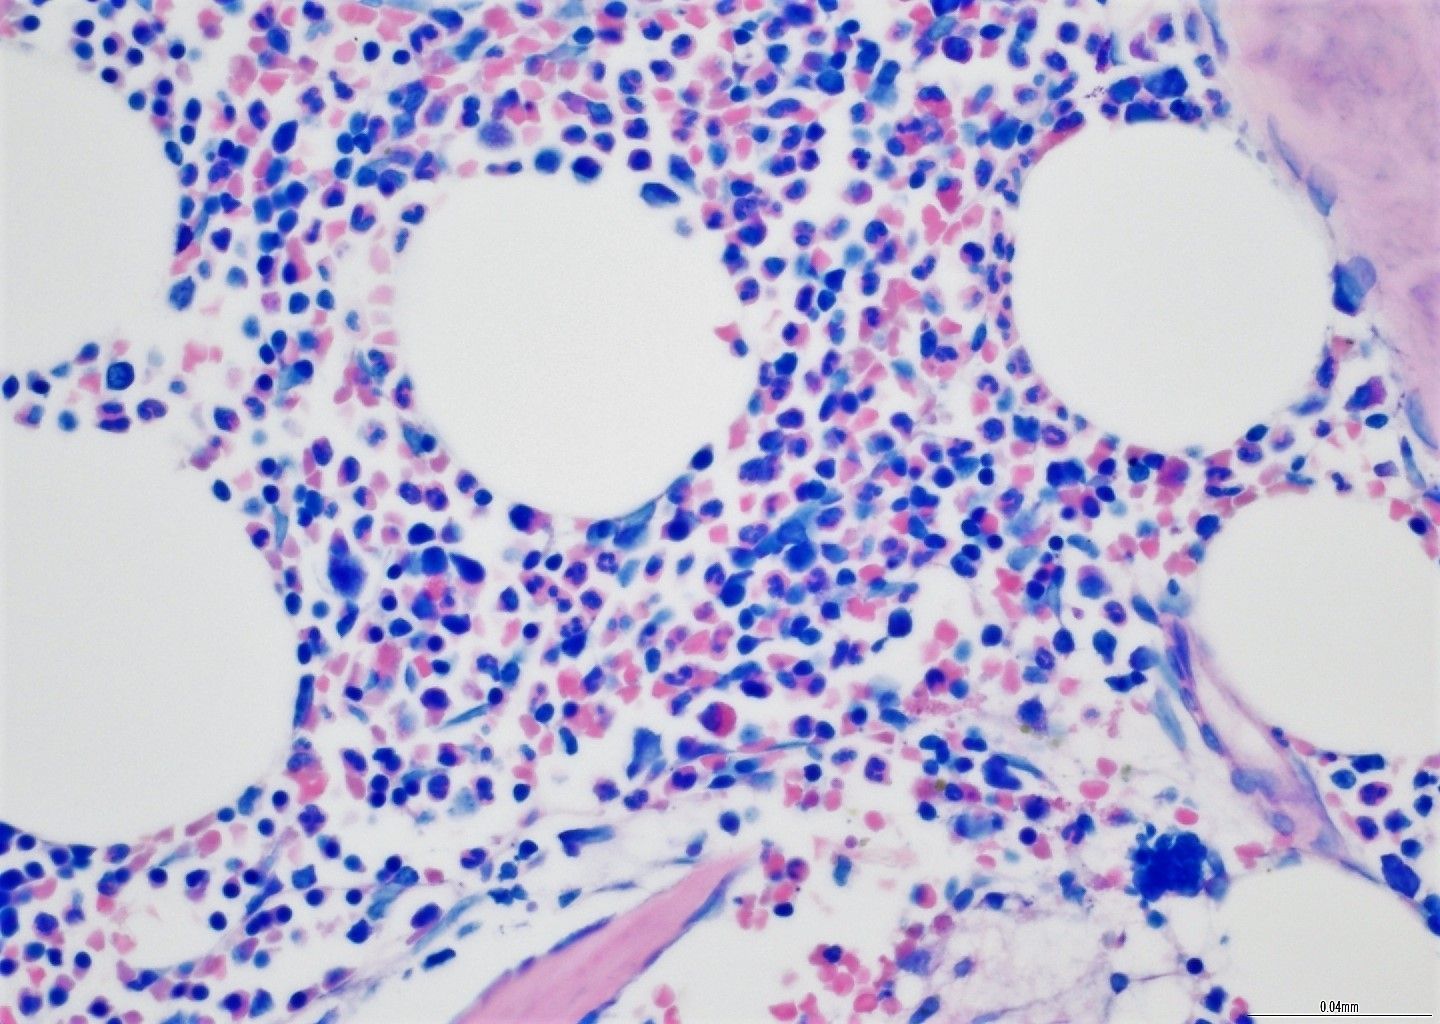

- Demonstracija specifičnih ciljeva krvnih stanica unutar biopsije BMT-a

- Dijagnostički polutanki rezovi smole